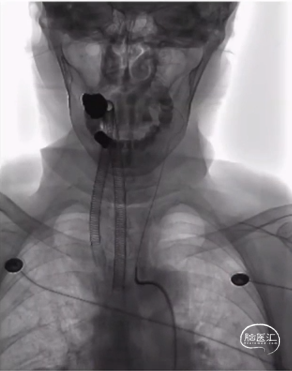

全麻下,右侧股动脉置入8F血管鞘,在泥鳅导丝及5F 单弯造影导管引导下将长鞘送至左侧颈内动脉起始,撤出造影导管。

6F SKATHI远端通路导管与长鞘同轴,在泥鳅导丝引导下将SKATHI远端通路导管送至左侧颈内动脉海绵窦段。

在Synchro14微导丝引导下将Gateway3.5-9mm球囊送至狭窄段,缓慢扩张球囊至6atm,撤出球囊压力后造影见狭窄改善。

交换送入XT-27支架微导管至左侧大脑中动脉M1段,顺支架微导管送入Neuroform EZ 4.0-20mm支架,准确对位并释放支架,造影见狭窄明显改善。

全麻下,右侧股动脉置入8F血管鞘,在泥鳅导丝引导下将长鞘送至右侧颈内动脉起始。

微导丝引导下将Echelon10栓塞微导管送至瘤腔,依次填入9-30、7-30、6-20弹簧圈三枚,予以疏松填塞。